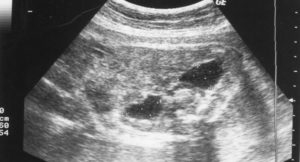

У плода при проведении ультразвукового исследования могут быть обнаружены увеличенные лоханки, чашечки почек, а также увеличенный мочеточник.

Соответственно, врач диагностирует три разных патологии: пиелоэктазию, пиелокаликоэктазию и уретеропиелоктазию.

Человеческий организм развивается по одной и той же схеме на протяжении миллионов лет, но есть ситуации, при которых внутриутробное развитие нарушается, и ребенок рождается уже больным. Патология почек у плода, как правило, носит название пиэлоктазия и заключается в расширении почечных лоханок.

Лоханки — это определенный участок почек, они напоминают собой резервуары, в которых скапливается моча, перед тем как отправиться в мочеточники и вывестись естественным путем. Если имеются какие-то сбои в выведении мочи из этих резервуаров, в процессе жизнедеятельности в них накапливается все больше, и больше жидкости.

Пиелоэктазия – это расширение лоханок из-за переполнения их мочой. Они становятся слишком маленькими, для поступающих в них больших объемов мочи и из-за этого растягиваются.